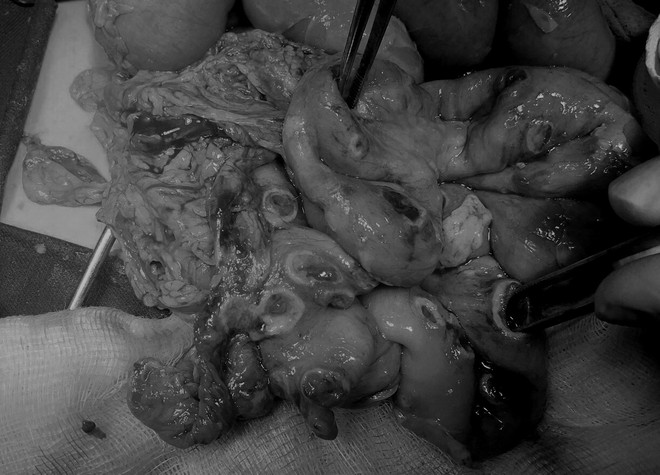

Bé trai bị thủng 50 lỗ ở ruột vì nhiễm ấu trùng giun từ chó mèo ảnh 2Trên 1 đoạn ruột dài 30cm của bệnh nhân có khoảng 50 lỗ thủng, đường kích 0,5-1cm. (Ảnh: PV/Vietnam+)

Nhiều chẩn đoán đã được đưa ra, sau đó, các bác sỹ nghĩ tới khả năng bệnh nhi nhiễm giun sán. Qua theo dõi, thăm khám cho bệnh nhân, các bác sỹ thấy trên 1 đoạn ruột dài 30cm có khoảng 50 lỗ với kích thước 0.5-1.5cm, xung quanh phủ giả mạc, niêm mạc tương ứng lẫn đỏ.

Các bác sỹ kết luận hình ảnh áp xe đường máu đa ổ ở thành ruột gây thủng, viêm mủ thanh mạc, phù hợp với ấu trùng giun tròn chó mèo.

Bệnh nhân được phẫu thuật cắt đoạn hồi manh tràng đưa 2 đoạn ruột ra ngoài làm hậu môn nhân tạo, lau rửa dẫn lưu ổ bụng.